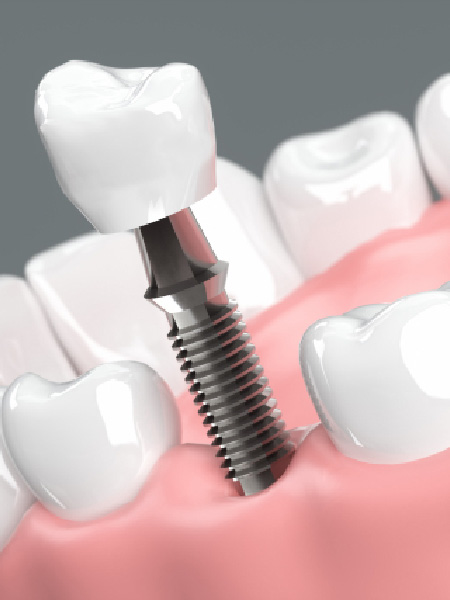

インプラント治療とは、失ってしまった自分の歯の代わりに、人工の歯根を顎の骨に埋め込み、その上に人工の歯を作製して噛み合わせを回復する治療法です。

固定性であるためガタついたりせず、自分の歯のように噛めるようになります。慣れるまでは多少違和感を感じることもありますが、その期間を過ぎれば、自然の歯に匹敵する機能が得られます。最新の歯科技術によって、自分の歯と同じように作ることが可能です。